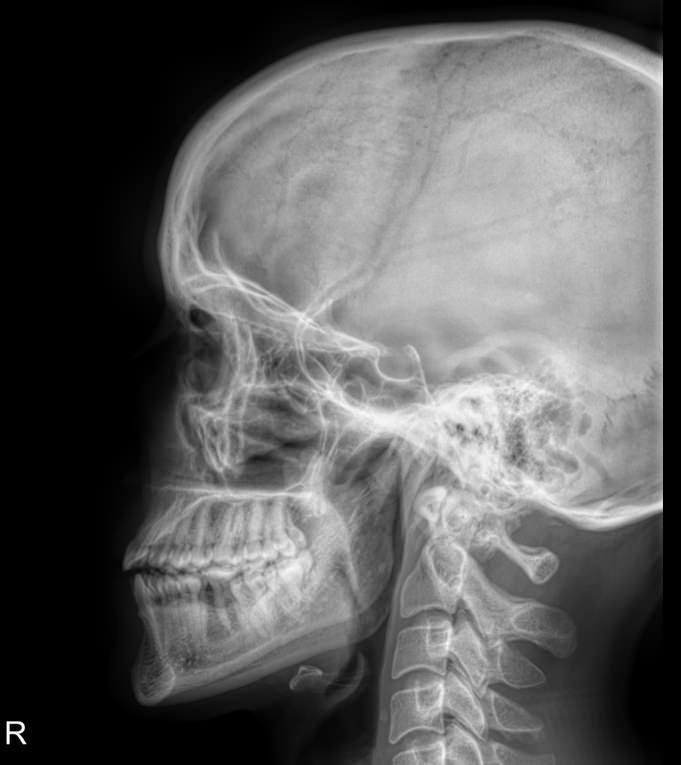

Первый вид обследования, который чаще всего назначают при подозрении на заболевания гипофиза ― рентгенография. На снимке будут четко видны изменения, которые позволят врачу выбрать способ лечения или дополнительные виды обследования.

Что покажет рентген хиазмально-селлярной области

• Изменение стенки: истончение, разрежение, выраженная деструкция;

• Дно: без изменений, неровный внутренний контур, углубленное;

• Клиновидные отростки: могут быть тоже истонченные;

• Внутренний контур: неровный, «двойной»;

• Могут быть изменены нормальные размеры: сагиттальный, вертикальный и их соотношение ― индекс седла.

Специально готовиться не надо. Однако необходимо снять с головы и шеи все металлические предметы: цепочки, заколки, серьги, съемные протезы и предупредить о несъемных. Также надо снять очки и расстегнуть верхние пуговицы на одежде. Затем надо надеть свинцовый фартук и сесть или встать к регистрирующей пластине боком. Снимок выполняется в боковой проекции, реже ― в прямой, как именно приложить голову, покажет рентгенолаборант.